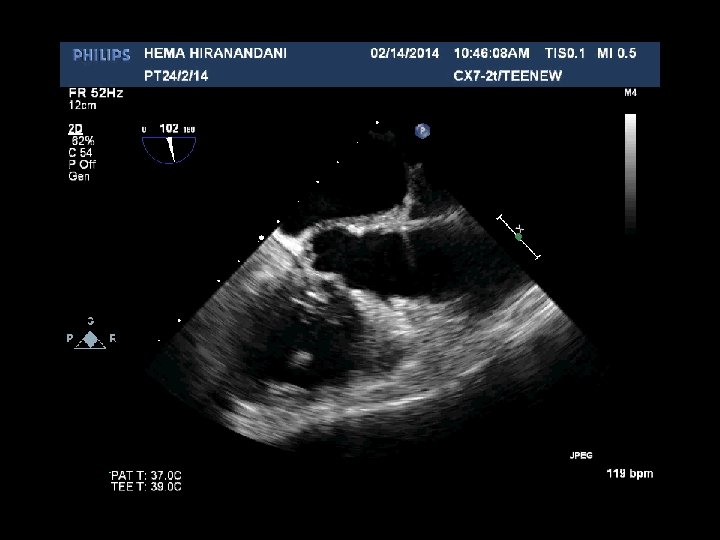

HEMA HIRANANDANI F 57 YRS • • • AVR BIO PROSTHETIC VALVE DEHISCENCE IE MULTIPLE VEGETATIONS ON BIO PRO VALVE AO ROOT ABSCESS SEVERE PARAVALVULAR AR RVSP= 37 mmhg

Hema Hirandani